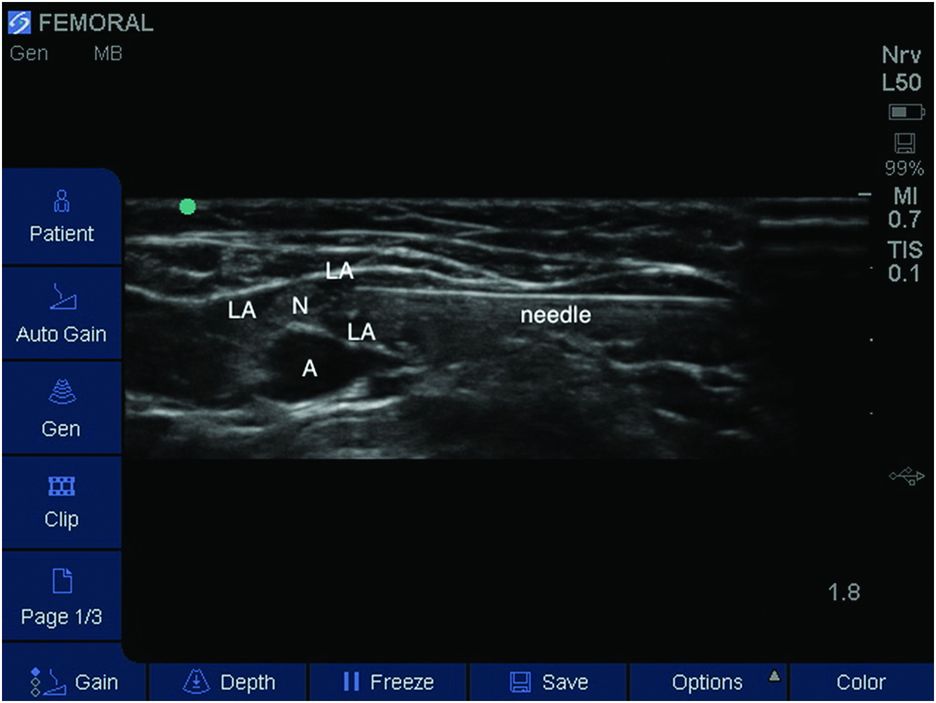

Ultrasound guide

Ultrasound guide 108 фотографий